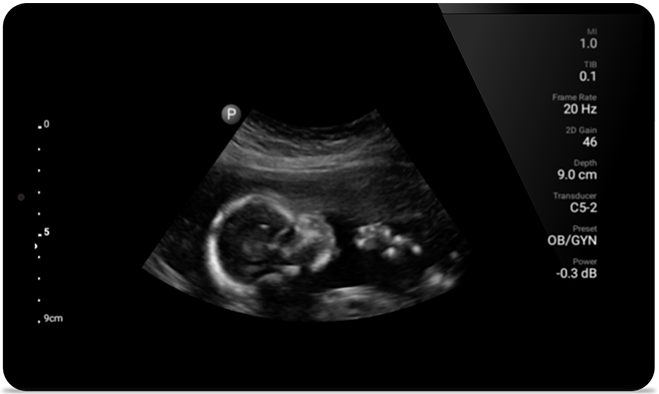

• 5 to 2 MHz extended operating frequency range • 50mm radius of curvature • 2D, color Doppler, M-mode, advanced XRES and multivariate harmonic imaging, SonoCT • High-resolution imaging for deeper applications: abdominal, gall bladder, OB/GYN and lung imaging preset optimizations • Center line marker • USB-C transducer with replaceable cable

From revealing the subtle details of an image to uncovering enriched tissue definition from multiple angles, Lumify can help you make real-time decisions with more confidence from assessment through recovery.